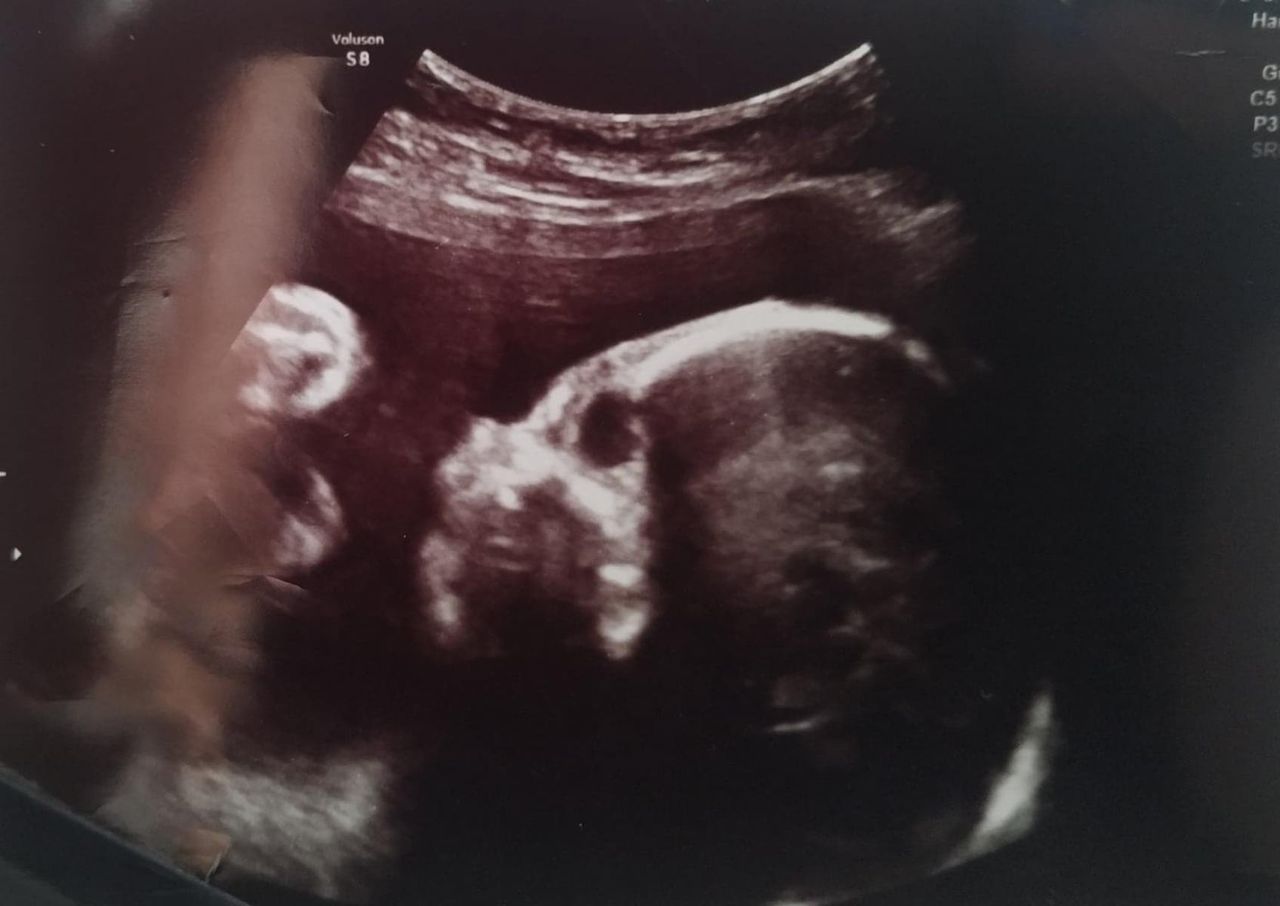

Dziewczynka przyszła na świat na początku lutego 2023 roku. O tym, że będzie chora, jej rodzice wiedzieli już w trakcie ciąży. Dowiedzieli się w 19. tygodniu.

Badania wykazały, że Hania ma zespół Edwardsa, czyli trisomię 18 - chorobę genetyczną, która wiąże się z licznymi wadami u dziecka, m.in. małogłowiem, niską masą, zniekształceniem małżowin usznych, małą żuchwą czy szerokim rozstawieniem oczu.